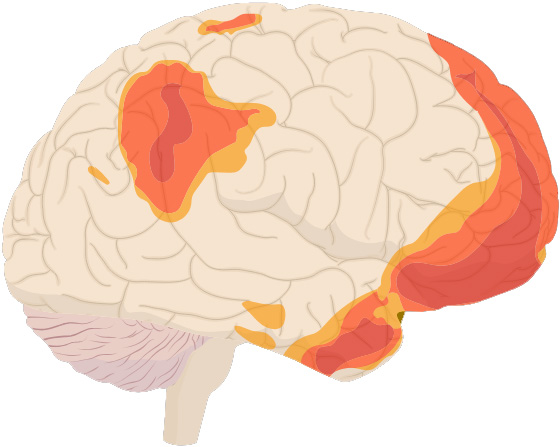

Bilim tarafınca tanımlanan ilk beyin ağlarından önde gelen varsayılan mod, dorsal ve ventral medial prefrontal korteksler benzer biçimde beynin ön kısmındaki birkaç bölgenin yanı sıra arka singulat korteks, precuneus ve angular girus benzer biçimde beynin çeşitli yerlerine dağılmış öteki bölgelerden oluşuyor. Bu bölgeler bellek, edinim tekrarı, tahmin, fiil değerlendirmesi, ödül/ceza ve informasyon entegrasyonu ile ilişkili. (Aşağıdaki görseldeki renkli alanlar, varsayılan ağ devreye girdiğinde daha etken hale geliyor.)